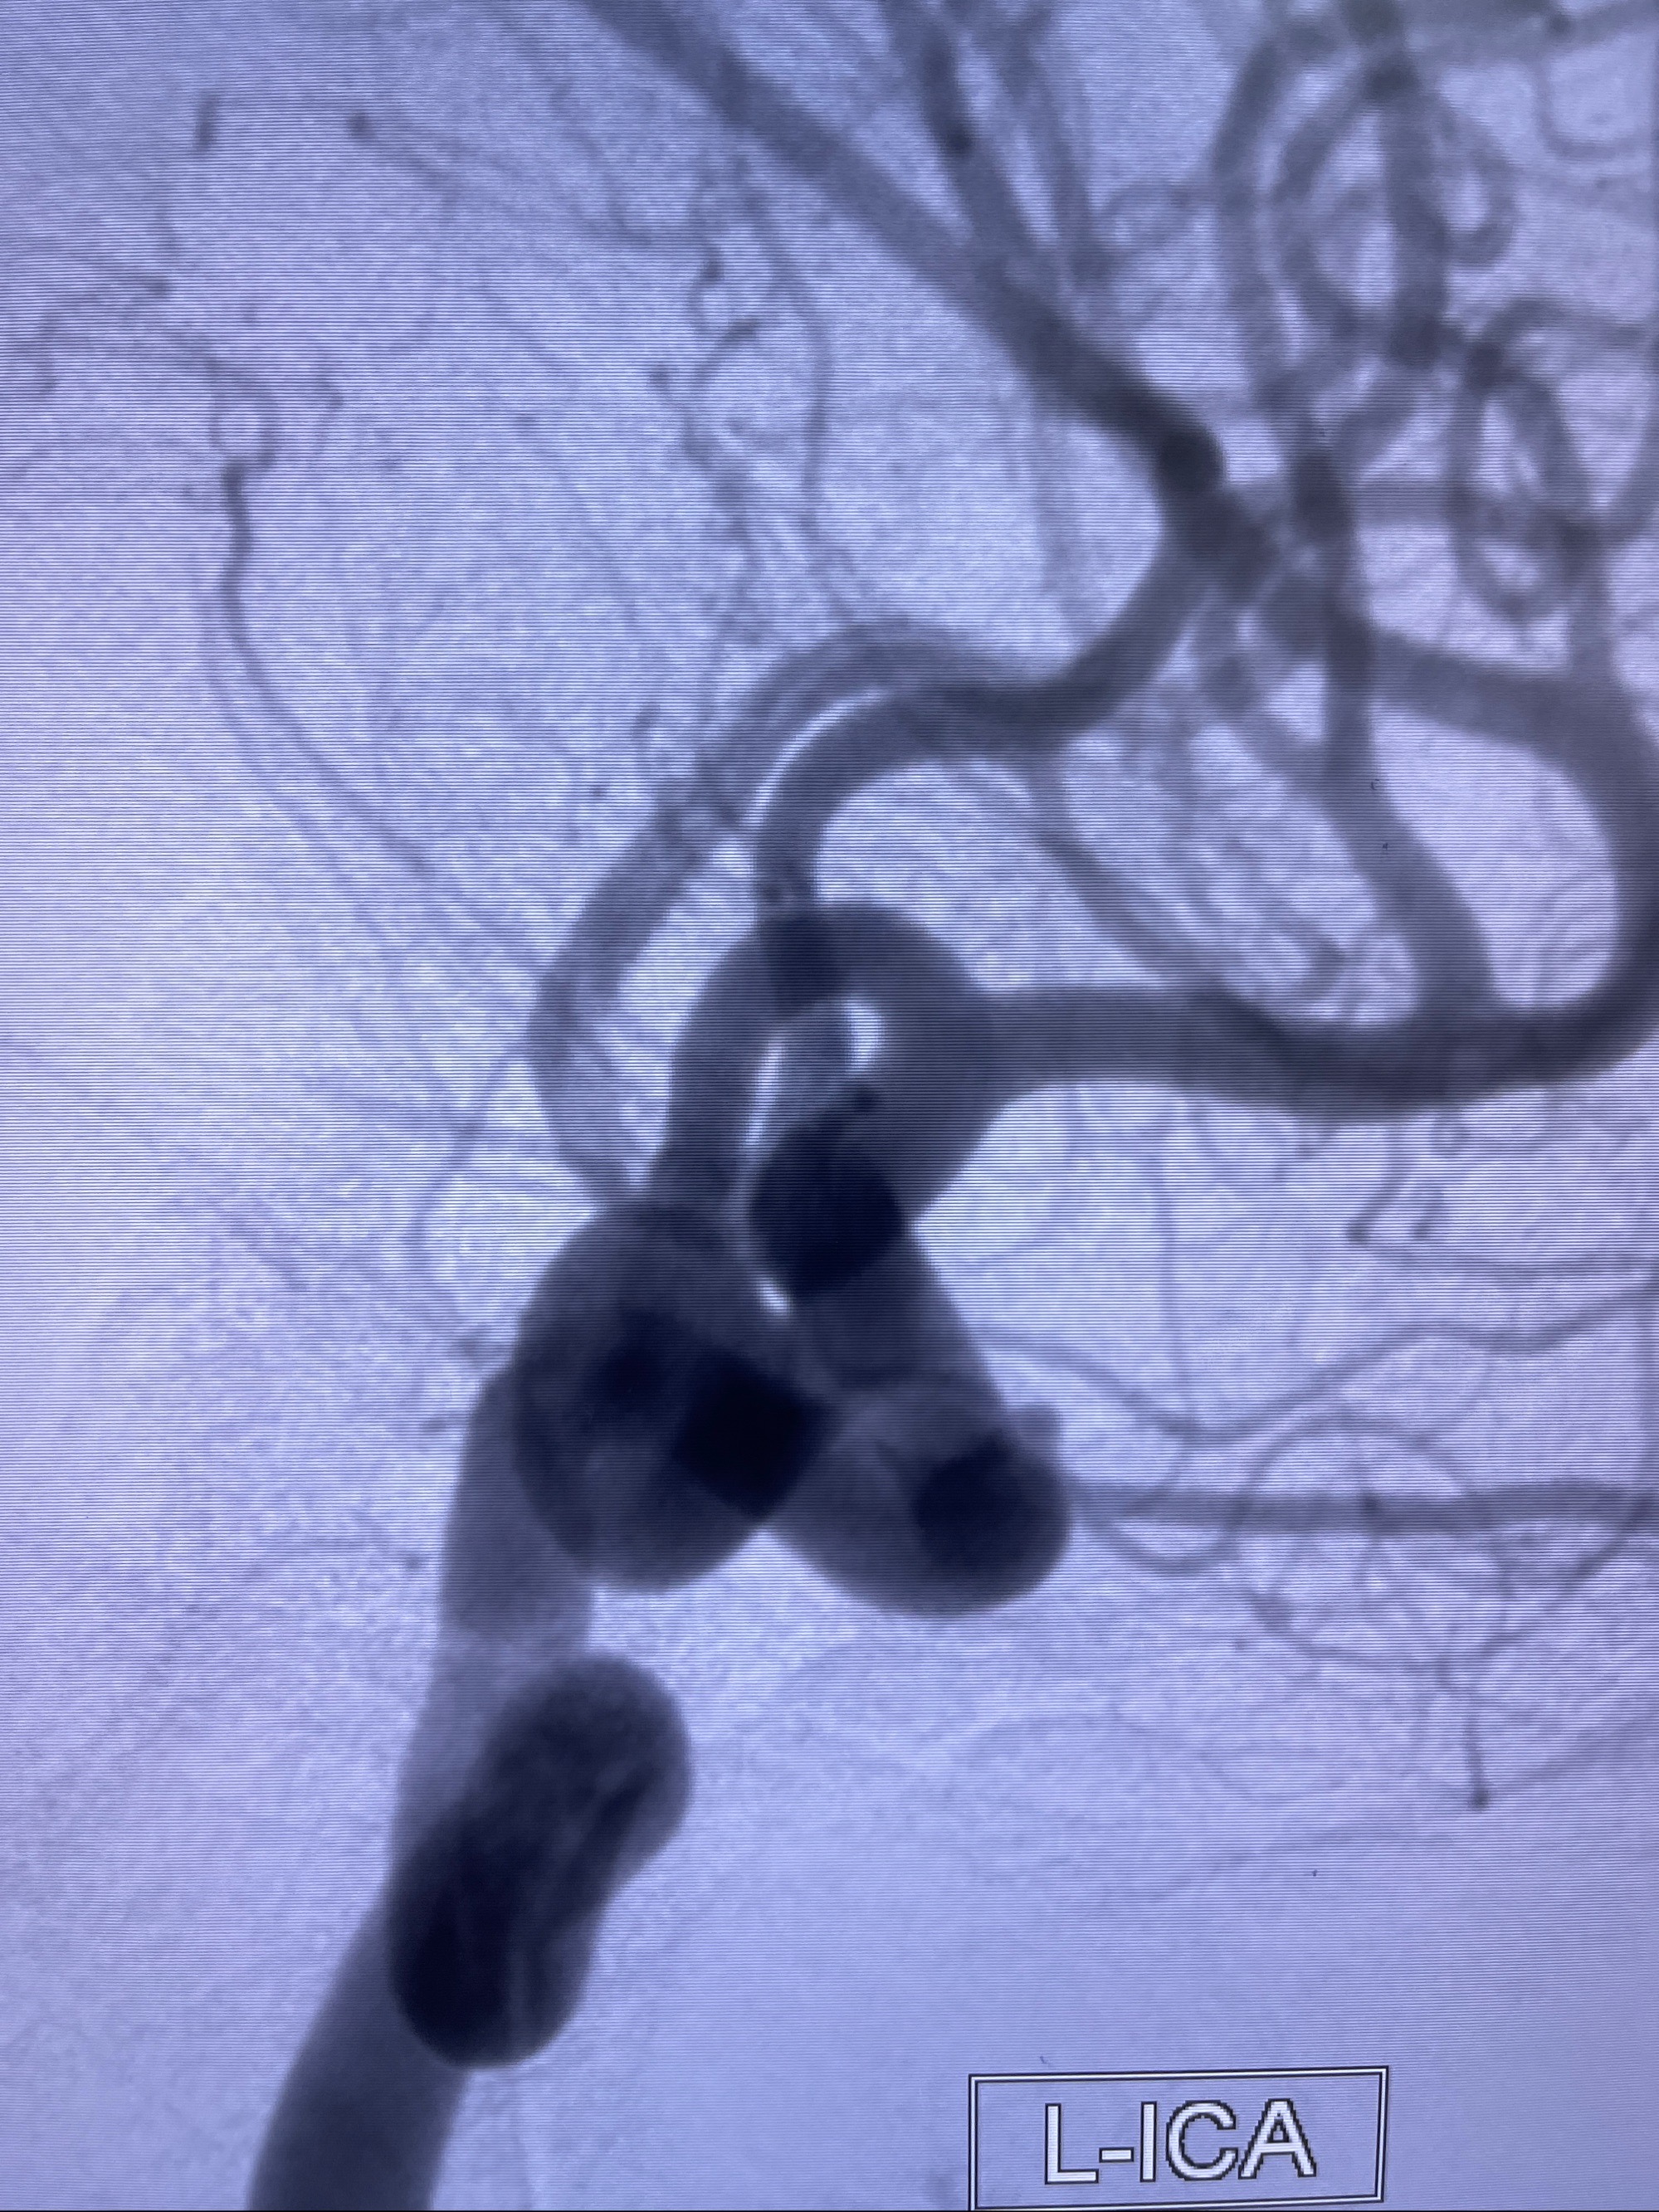

2023-08-30DSA:左侧颈内动脉眼动脉动脉瘤,约3*9.2*7.3mm大小

2023-09-06全麻下行左侧颈眼动脉瘤

密网支架辅助栓塞

术后3D显示支架贴壁佳